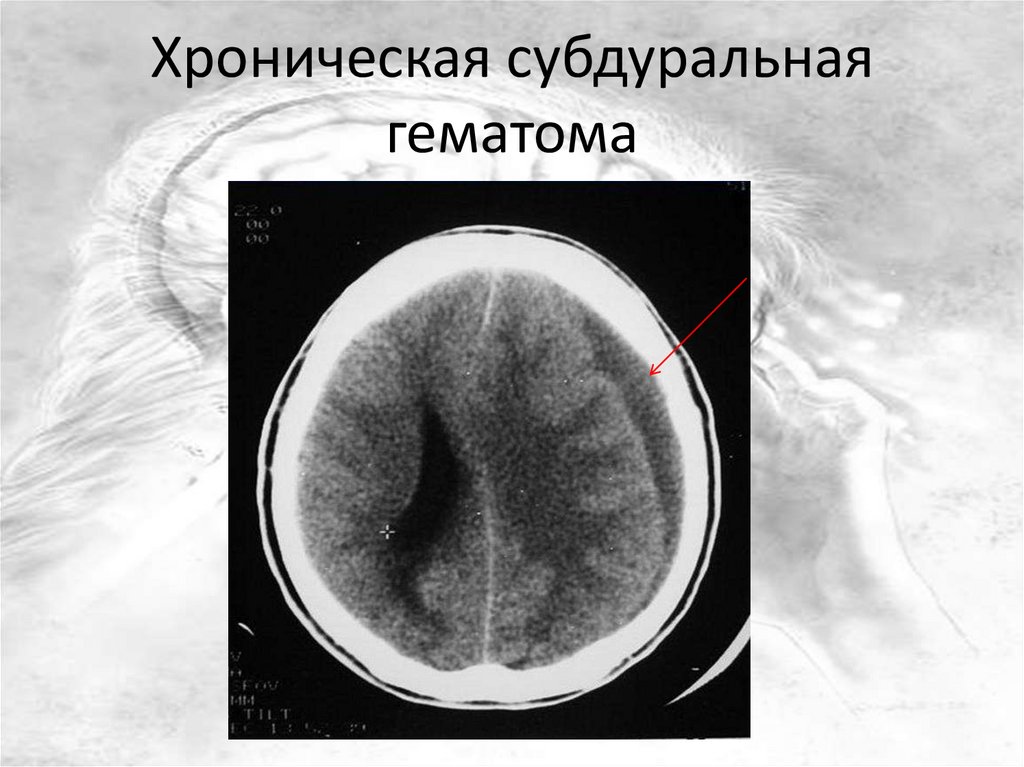

Хроническая субдуральная

гематома